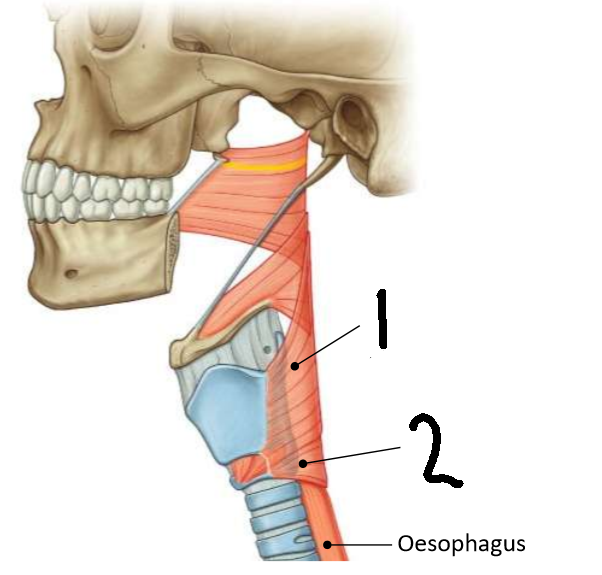

What muscle is this?

inferior constrictor

Which part of the muscle is 1?

thyropharyngeus

Which part of the muscle is 2?

cricopharyngeus

What are the attachments of this muscle?

oblique line of thyroid cartilage, cricothyroid tendon, cricoid cartilage → pharyngeal raphe